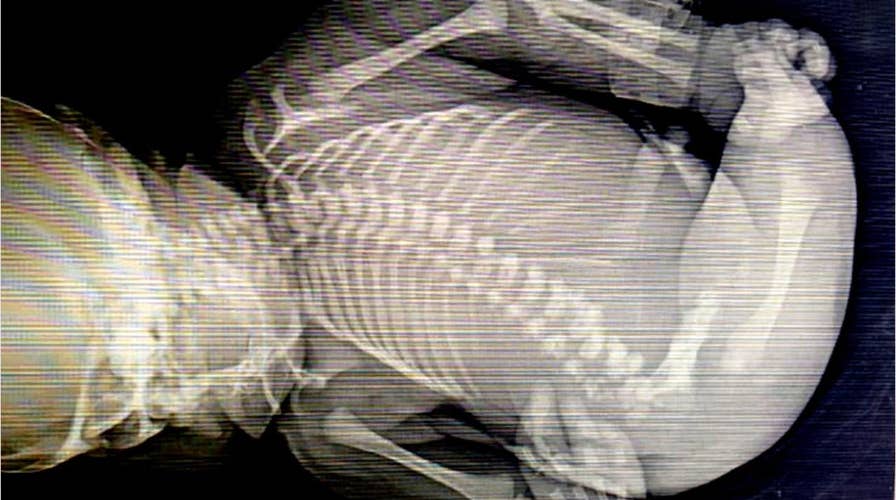

A baby born with "Mermaid Syndrome" died minutes after birth. What is the rare condition?